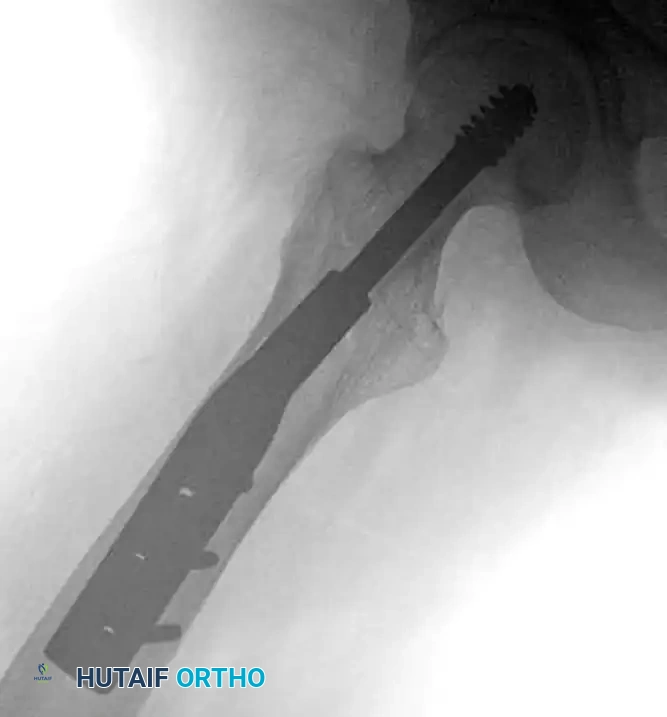

Intramedullary Nails (Cephalomedullary Devices)

Unstable intertrochanteric femoral fractures (A3, reverse obliquity, and highly comminuted A2 fractures) are biomechanically best treated with an intramedullary implant, such as a Gamma nail or an intramedullary hip screw (IMHS).

The theoretical benefits of intramedullary nails over side-plate devices include:

* Improved Biomechanics: A shortened lever arm reduces bending moments on the implant.

* Minimally Invasive: Smaller incisions lead to decreased blood loss and soft tissue stripping.

* Lateral Wall Bypass: The nail acts as an internal buttress, preventing excessive medialization even if the lateral wall is incompetent.

While early meta-analyses suggested side plates were superior due to complications like distal femoral fractures at the nail tip, modern, anatomically bowed second- and third-generation cephalomedullary nails have largely mitigated these risks.